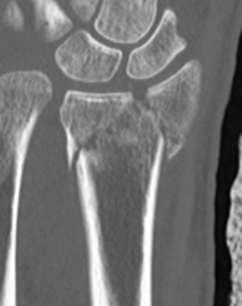

| 3 columns | Three articular surfaces |

Radial column with scaphoid fossa and radial styloid

Intermediate column with lunate fossa and sigmoid notch

Ulna column with TFCC and distal ulna |

Scaphoid facet

Lunate facet

Sigmoid notch |

Radial angles

| Volar tilt mean 11° | Radial inclination mean 22° | Radius mean 11 mm longer than ulna |